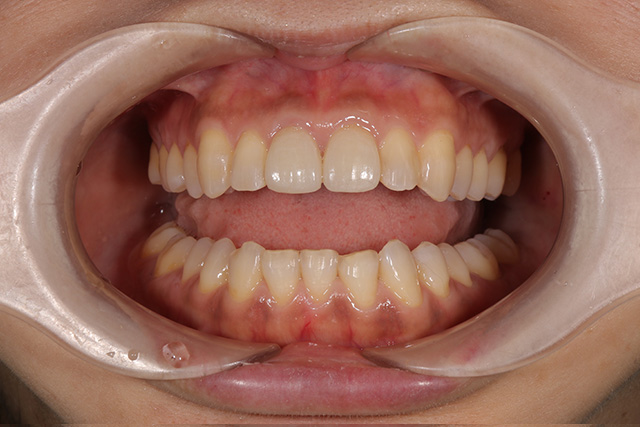

審美症例